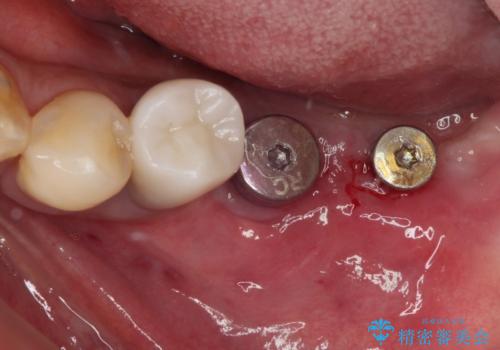

- 一度治療を終えたものの、奥歯へインプラントの追加を希望された患者様です。

最後臼歯部にインプラントを1本追加埋入し、2歯連結のクラウンにて補綴治療を行うこととしました。

インプラント埋入後、手前のインプラント周りの丈夫な歯肉(角化歯肉)が失われてしまったため、角化歯肉の移植を行うこととなりました。